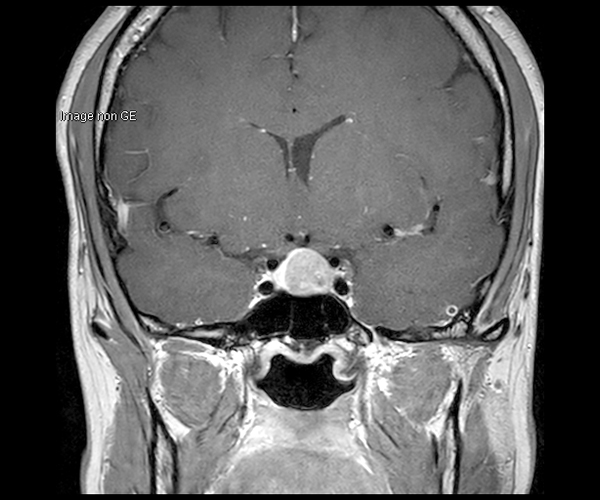

L’amélioration de la résolution spatiale s’applique à l’exploration morphologique des hippocampes dans le diagnostic de la maladie d’Alzheimer, à la détection de petites lésions de sclérose en plaques ou de métastases, à l’étude fine du cortex dans les épilepsies.

L’augmentation de l’effet de susceptibilité magnétique à plus haut champ permet d’améliorer la détection des hémorragies et est utilisé également dans l’imagerie de perfusion (tumeurs) et l’IRM fonctionnelle (BOLD). L’allongement du T1 à plus haut champ entraîne une meilleure saturation des tissus statiques et par conséquent une augmentation du contraste sang/tissus dans l’AngioIRM.